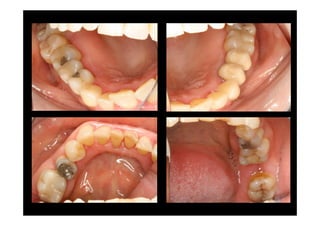

BASELINE

Baseline X-ray